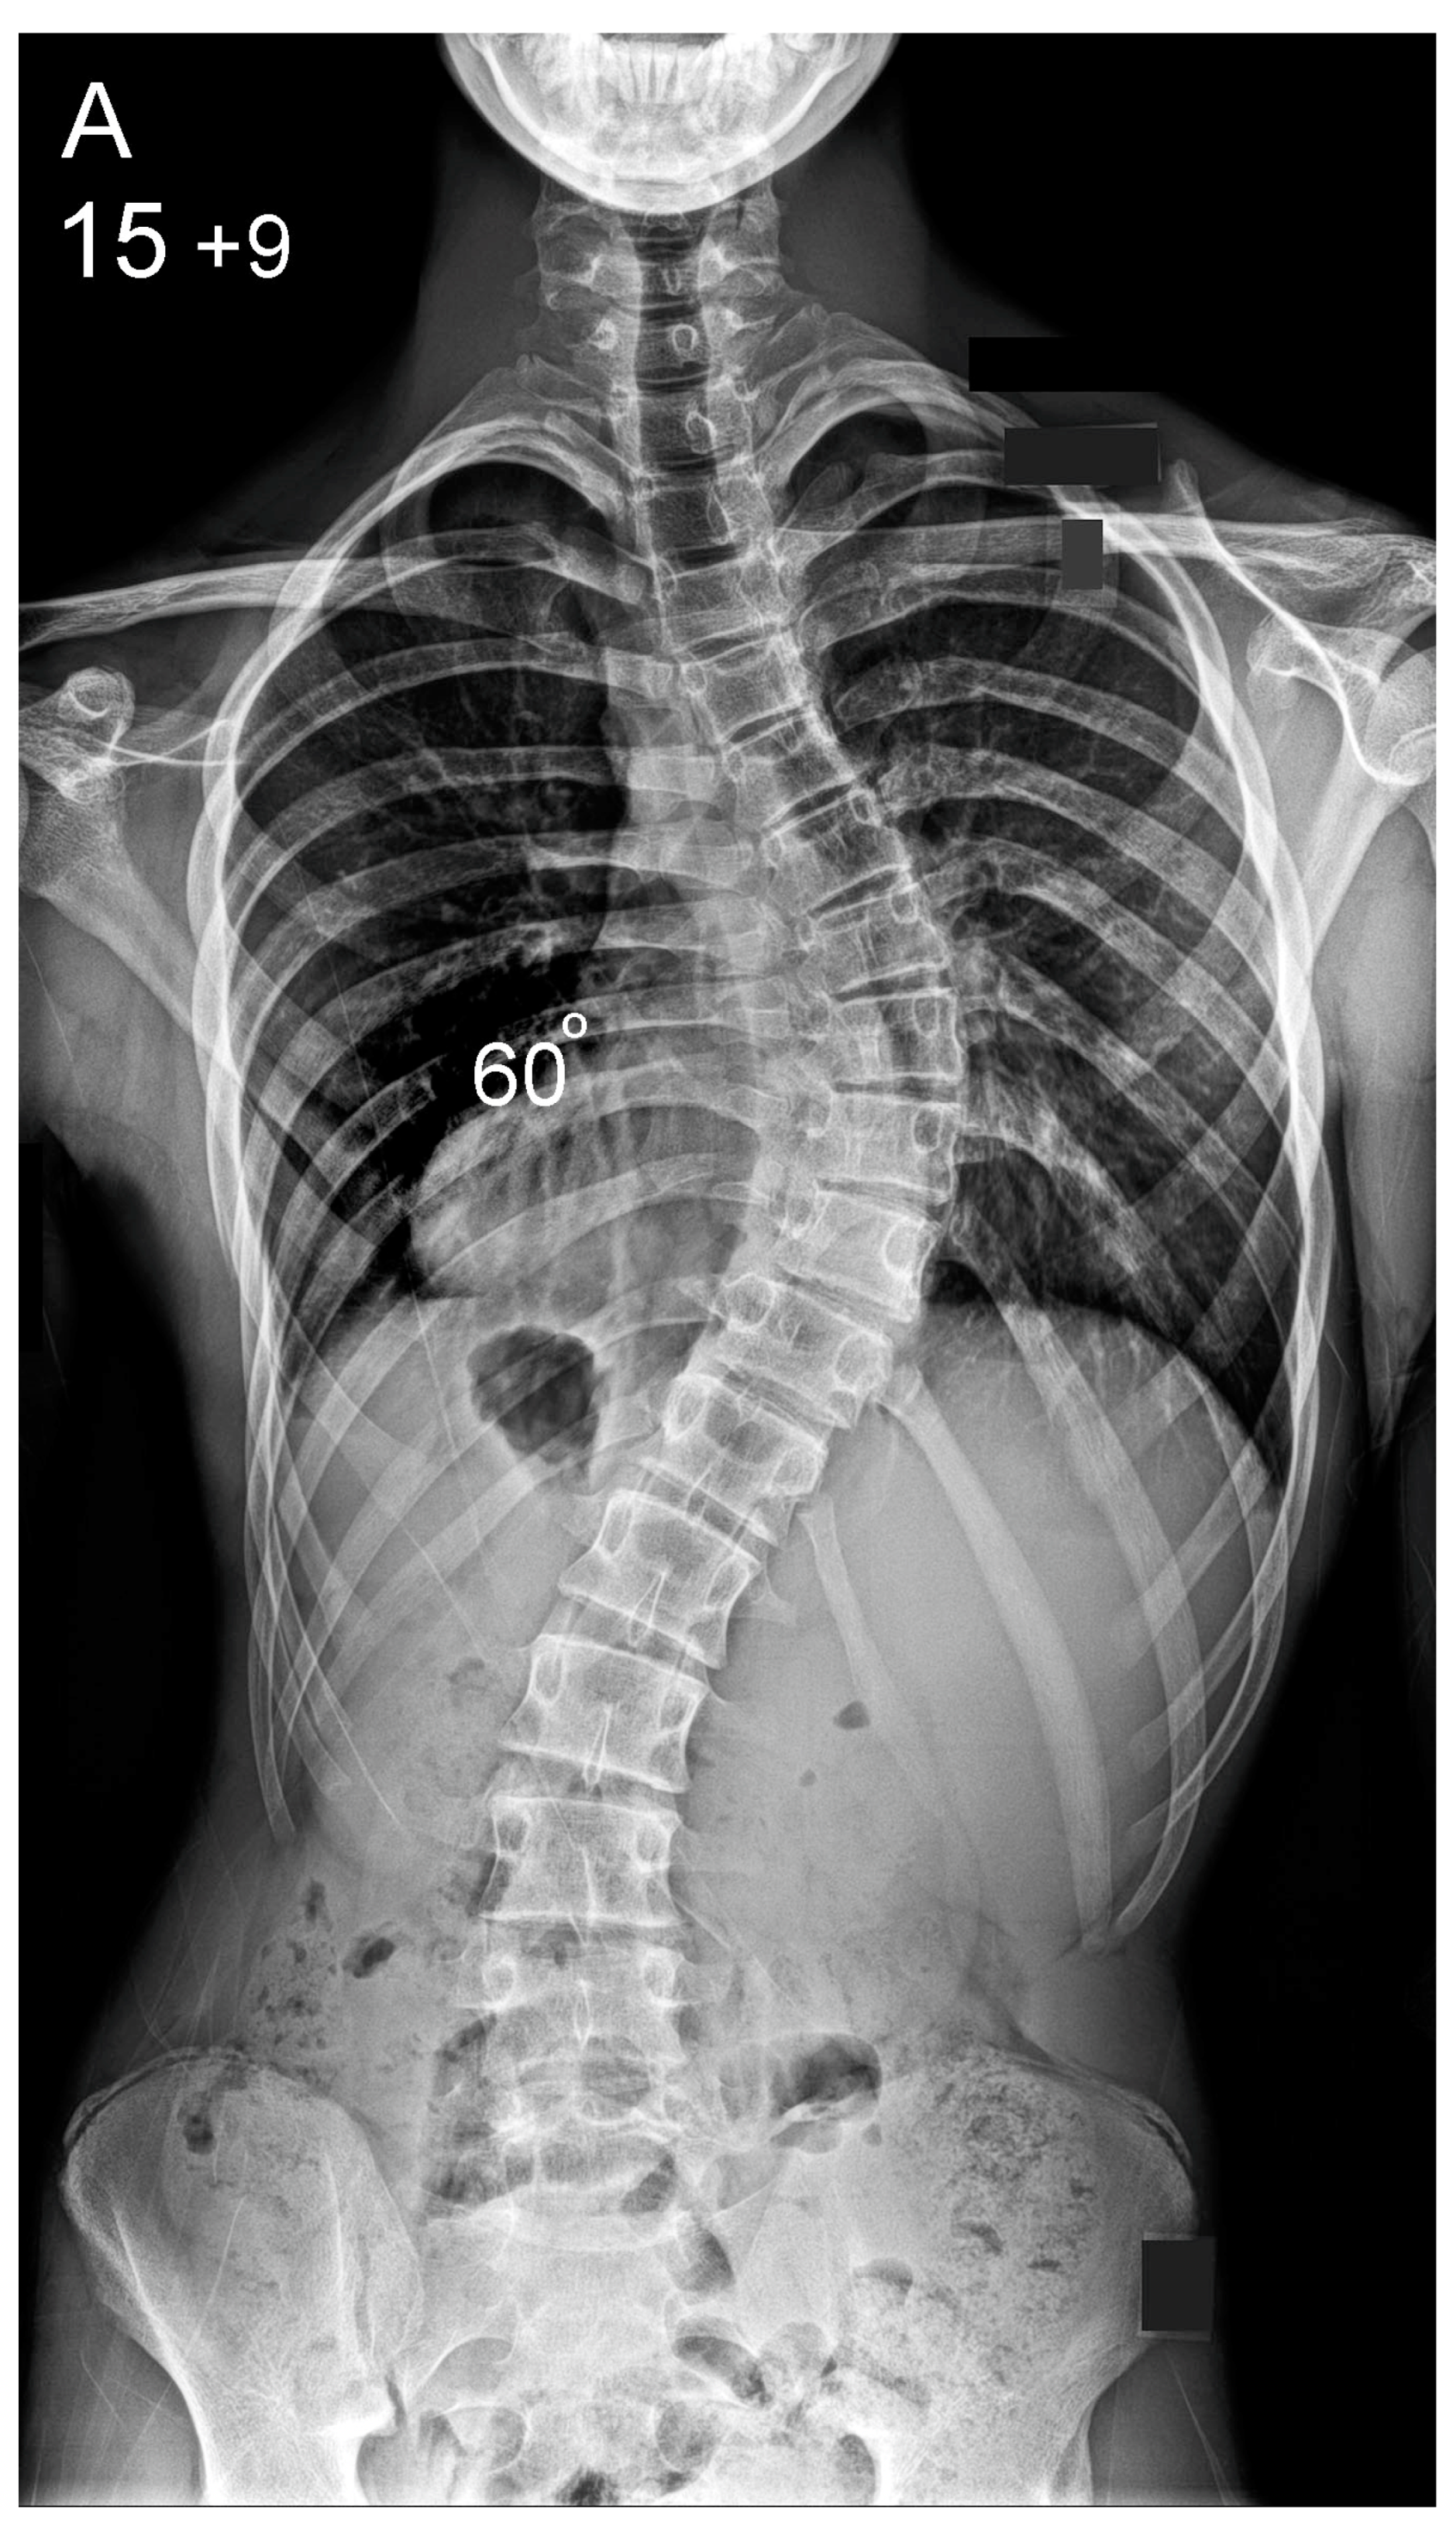

Figure 1.

Patient aged 15 years and 9 months with a right thoracic AIS producing thoracic translocation and listing of the trunk to the right, as well as thoracic flat back producing negative global sagittal balance of the spine and compensatory cervical kyphosis (A,B). The patient underwent posterior scoliosis correction using the AS technique which restored segmental and global coronal/sagittal spinal balance at latest follow-up (age 18 years and 8 months) into adult life (C,D). Clinical photographs demonstrate excellent correction of the coronal deformity and associated rib hump after scoliosis surgery (E–H).